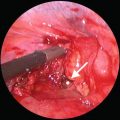

Fig. 36.3

(a, b) Insert: bullet track in pulmonary tissue. Main sketch: tractotomy using staplers